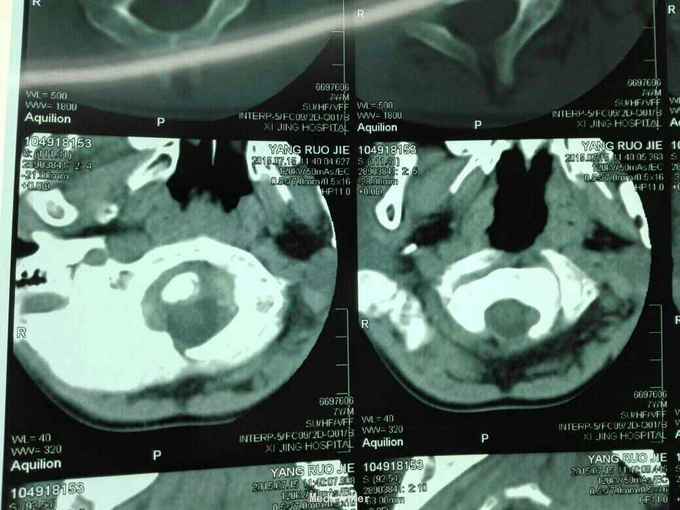

先天脊柱畸形

先天脊柱畸形8年。